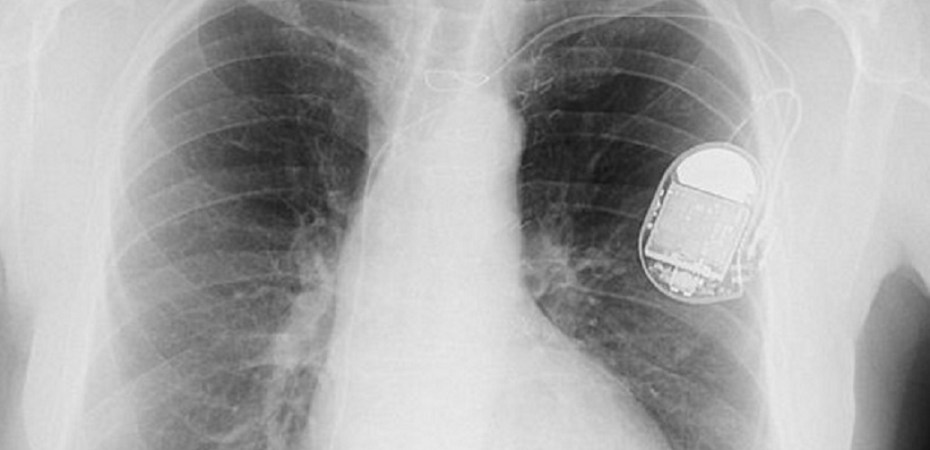

(ANTIMEDIA) Hamilton, OH — An Ohio man pleaded not guilty to arson charges Tuesday after police arrested him, in part, based on information obtained from the man’s pacemaker. According to officials, 59-year-old Ross Compton stands accused of burning his home down on September 15 and faces charges of aggravated arson and insurance fraud.

Police say they obtained a warrant to search all electronic information stored on Compton’s pacemaker when he gave statements that were not consistent with the evidence found at the fire. He told authorities that he packed belongings when he saw the fire, threw them out of a window and carried them to his car.”  According to court documents, a cardiologist who reviewed the data on the pacemaker determined “it is highly improbable Mr. Compton would have been able to collect, pack and remove the number of items from the house, exit his bedroom window and carry numerous large and heavy items to the front of his residence during the short period of time he has indicated due to his medical conditions.”